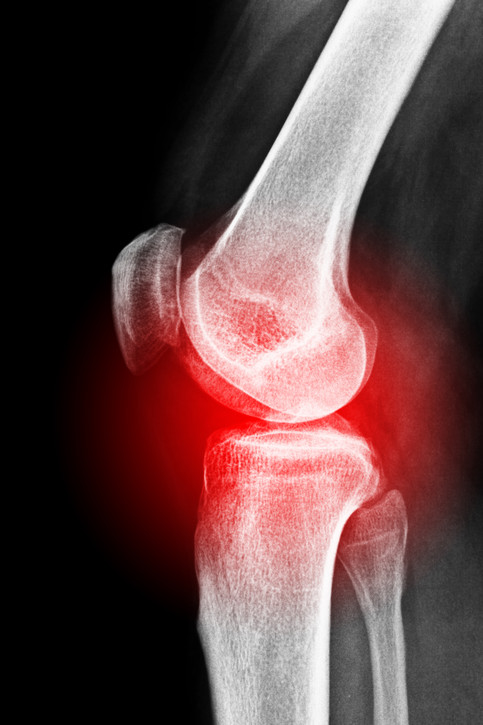

Pseudoartrosi

La pseudoartrosi si verifica quando un osso fratturato non si consolida.